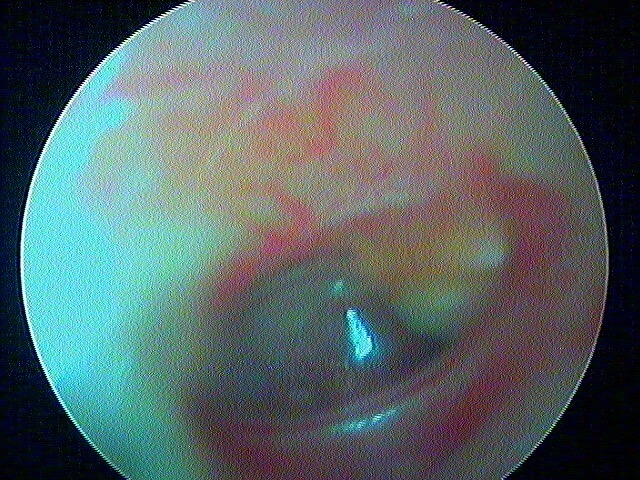

8 POCHE DE RÉTRACTION (ou ATÉLÉCTASIE)

C'est volontiers dans mon expérience la pathologie la plus importante et la plus difficile du diagnostic otoscopique pur. On bascule entre la surveillance clinique annuelle (abstention thérapeutique) et l'interventionnisme chirurgical pour éviter le cholestéatome (qui parfois est iatrogène pour l'audition résiduelle).

J'utilise plus le terme de poche de rétraction plutôt qu'otite atéléctasique.

Donc il faut caractériser ces poches de rétraction (+/- associée à myringosclérose, perforation tympanique, OSM) par:

1/autonettoyante: non cholestéatome

2/ mobilisable au Valsalva: pas d'aérateur (juste surveillance annuelle)

3/ contrôlable à l ’optique: pas de tympanoplastie (DANGER si on ne voit pas le bout de la poche qui s'invagine: risque de cholestéatome)

4/ localisation: pars flaccida (rétraction atticale ou épitympanique) ou pars tensa (rétraction atriale ou mésotympanique)